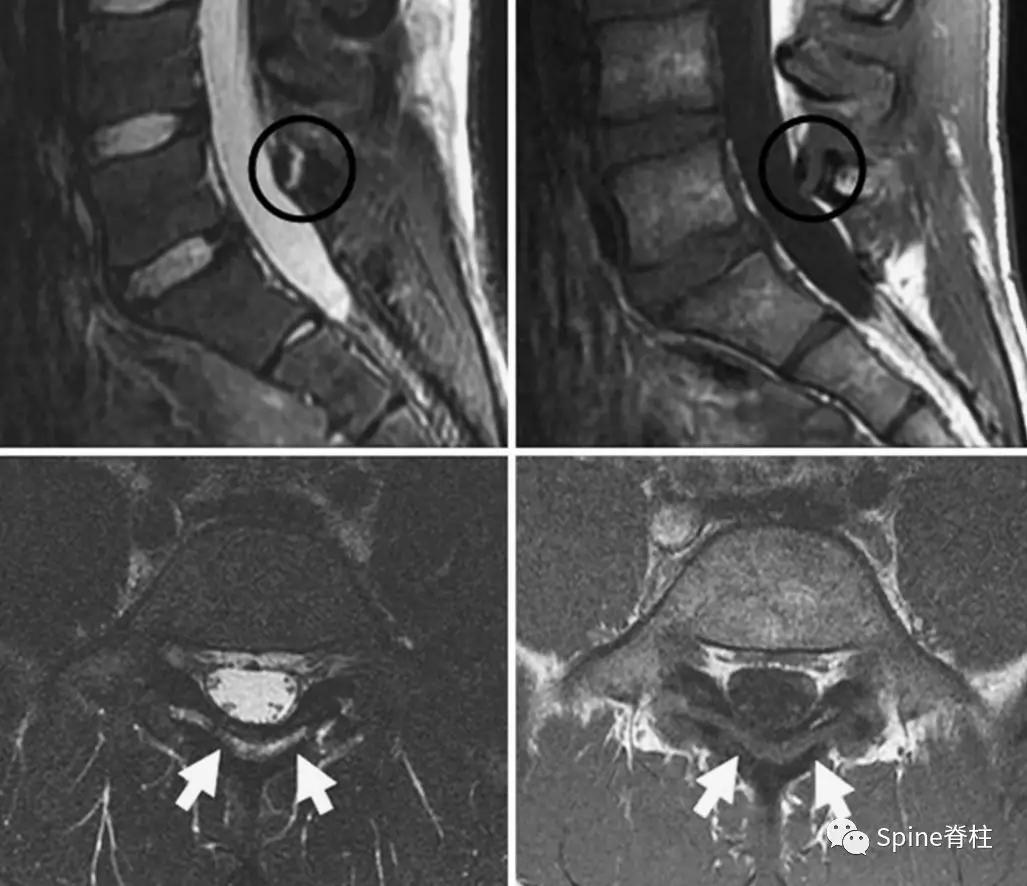

- 椎弓根出现T2高信号改变

Sairyo教授研究发现磁共振上 椎弓根出现T2高信号改变 (High signal changes) 是青少年和儿童峡部裂的早期诊断征象 。同时,存在椎弓根高信号改变也是保守治疗后能达到骨性愈合的良好预测指标(也就是说存在T2椎弓根右高信号改变的峡部裂患者,其峡部裂经保守治疗愈合的可能性大)。

图:右上图为椎弓根高信号改变(+),右下图为(-)

右图提示椎弓根高信号改变(箭头)

右图提示双侧椎弓根高信号改变(箭头)

右图:右侧椎弓根高信号改变明显,左侧椎弓根轻微高信号

因此, Sairyo教授也提出,对于青少年腰痛患者行MRI检查时,在传统椎间盘层面的基础上(A-C线), 多加一个经椎弓根层面(D线) (影像科医生希望能看到) 。因为,A-C线椎间盘层面可很好看出青少年腰椎间盘突出和腰椎椎体后缘离断症,而D线经椎弓根层面可以早期诊断出腰椎峡部裂和腰椎椎弓根损伤。